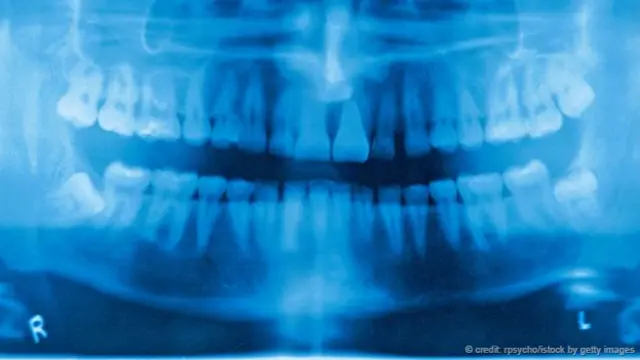

英国人的牙口真的很差吗?

关于英国人牙口不好的笑话可谓数不胜数,还有一部间谍电影也曾专门拿此事开涮,甚至连一些英国人自己都不否认这一点。在很多人看来,英国人跟烂牙简直就是天生一对。据说,你甚至可以根据牙齿判断一位英国影星是否去了好莱坞,因为他们会突然之间在微笑时露出洁白、整齐的牙齿。

然而,统计数据显示的究竟是什么结果?首先,这取决于你所谓的“烂牙”是何含义。对牙齿进行美白或矫正其实只是一种时尚。从口腔卫生的角度来看,关键在于有没有蛀牙。以这一指标来衡量,英国的情况其实好于很多国家——也包括美国。